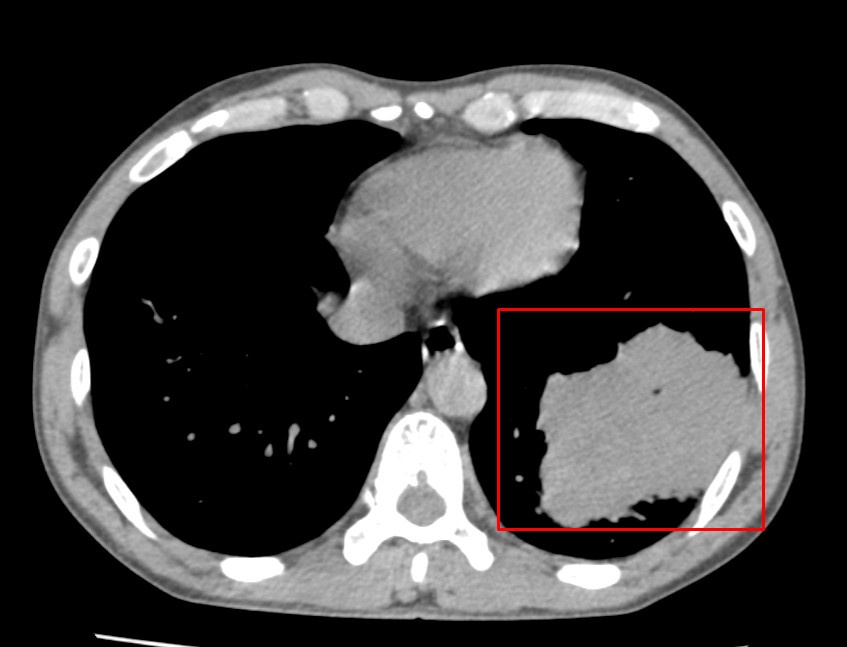

Kết quả kiểm tra cho thấy phim chụp CT lồng ngực của bệnh nhân có hình ảnh khối u thùy dưới phổi trái kích thước 73 x 80 mm. Chính bệnh nhân cũng rất bất ngờ với kết quả khám của mình.

Kết quả chụp CT lồng ngực của bệnh nhân. Ảnh: BVCC.